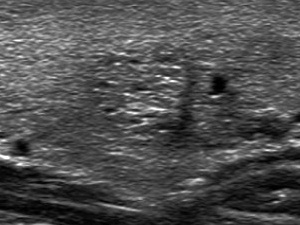

Connective tissue

Connective tissue is the essential part of the human organs therefore we can find it in every thyroid nodule, as well. The ultrasound hallmark of connective tissue is the synchronous presence of lines and granules depending on the angle between the transducer and the connective tissue. A fine spiderweb-like pattern is almost always seen within nodules and is caused by thin and short pale lines and tiny granules (<1mm). We use the term non-specific hyperechogenic figure for this normal finding. Thick and bright hyperechogenic granules and lines are signs of thickened connective tissue.

Proliferation of connective tissue is frequently seen in Hashimoto's thyroiditis but might occur even within a nodule. The brightness of the fibrotic figures varies but tends to be less than that of the microcalcifications. Nevertheless, granules corresponding to fibrosis are often misinterpreted as microcalcifications because the researcher does not always notice the synchronous presence of hyperechogenic lines.

Also, it is more difficult to visualize or if it is visualized, then to appreciate a linear or curved structure than a granule because the former requires that we place the transducer almost parallel of the structure, so in most cases of fibrosis the granules predominate over lines. It means that an important differential diagnostic problem arises in the predominance of hyperechogenic granules: the differentiation between microcalcification and proliferation of the connective tissue. Except for the localization, the presentation of this echogenic figure is identical with that of back wall cystic figures. However, proliferation of connective tissue is found in solid parenchyma while the latter in the dorsal wall of cystic areas. The distinction between these figures is not always possible, but it has minimal if any relevance.